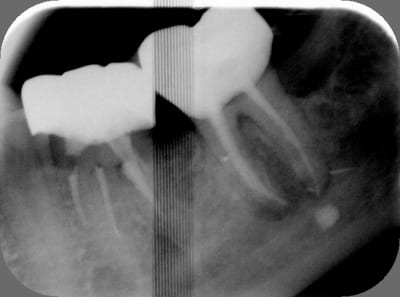

Sethef

17/05/2014 à 15h35

Bon allez, je le kiffe.

Et la pâte dans le dentaire inf c'est pas de moi.